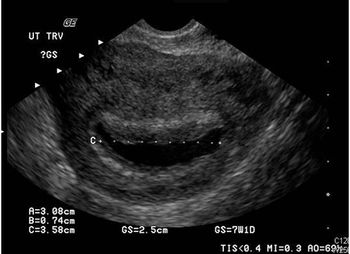

The pain and bleeding have persisted for 2 days. She last menstruated 5 weeks ago but doubts she is pregnant. Take a close look at the ultrasound image. Your Dx?